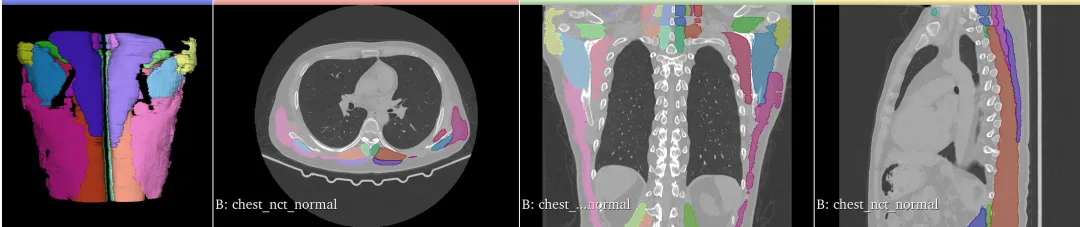

胸部肌肉分割: